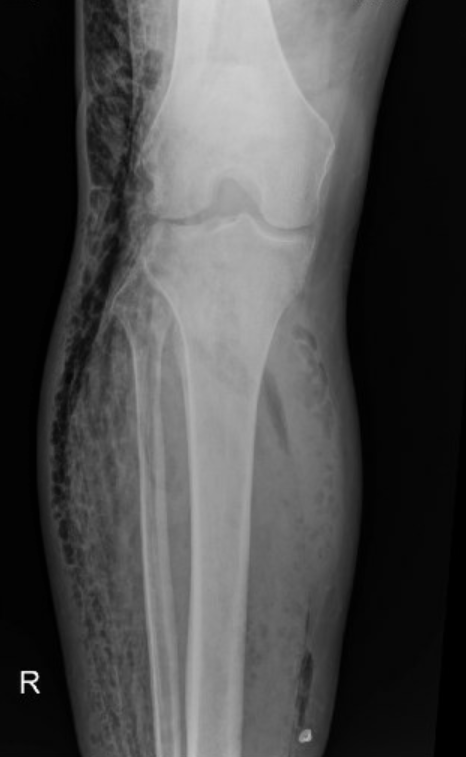

Below is a case of extensive right lower extremity necrotizing fascitis with diffuse subcutaneous emphysema.